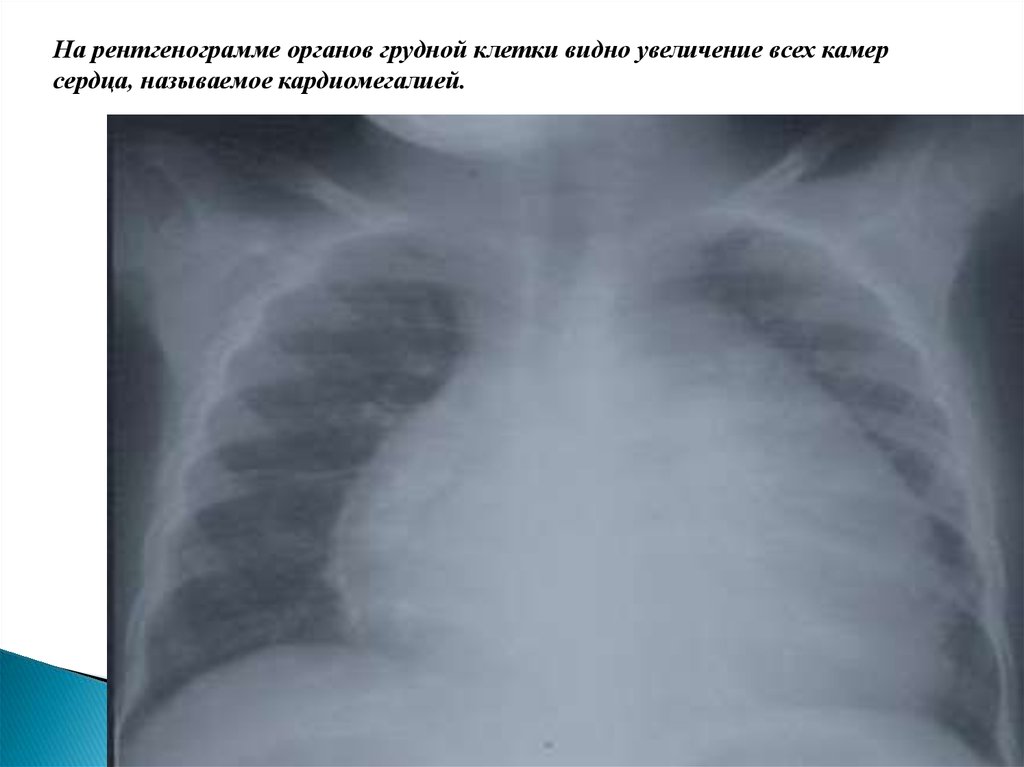

- рентгенография органов грудной полости – может показать расширение тени сердца в связи

с гипертрофией миокарда или дилатацией желудочков, изменения в нижних отделах легких

или по всем легочным полям (признаки венозного застоя или отека легких соответственно).

На рентгенограмме органов грудной клетки видно увеличение всех камер

сердца, называемое кардиомегалией.